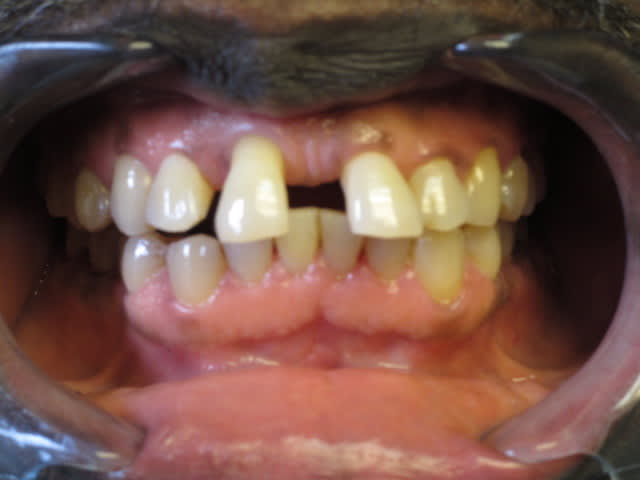

- Patient 53 ans, non fumeur, bonne santé générale.

- Consulte pour 11 "légèrement mobile et qui vient toucher sa lèvre inférieure".

- Reste de la bouche plutôt sain, quelques soins, pas de prothèse, pas de dents manquantes.

- grosses usure amélaire sur les molaires (type ruminant!)

ca sent la parodontite agressive.

visiblement peu de plaque et de tartre, et le patient s'est rendu compte de la progression de la maladie parodontale, ce qui veut dire que c'est assez rapide. Il faudrait quand meme la pano et un charting pour confirmer le diagnostic.